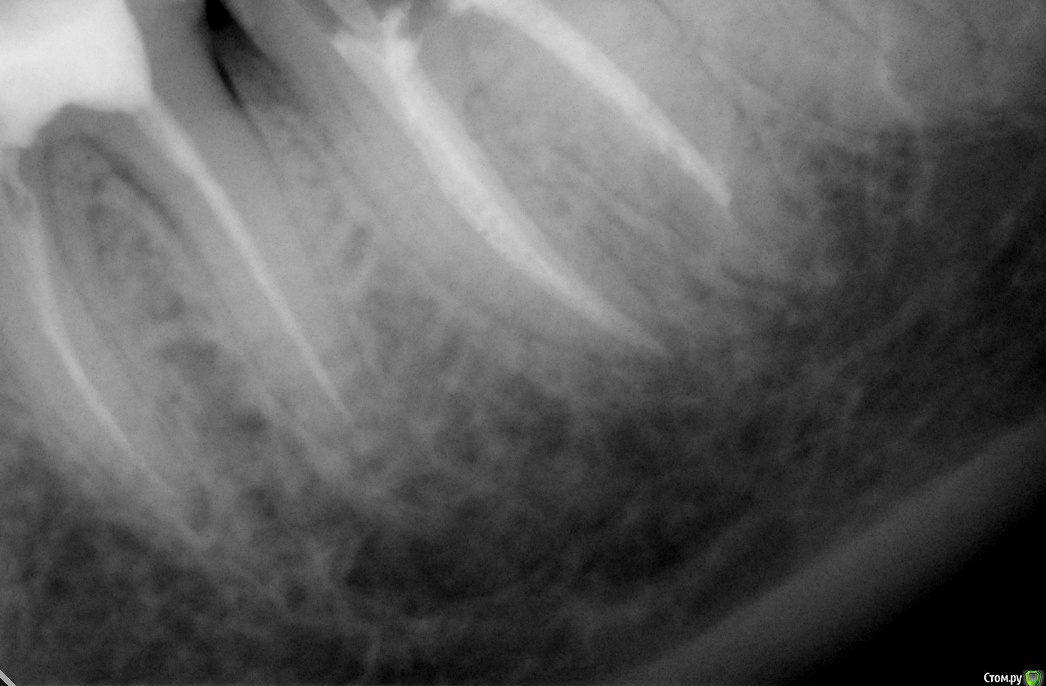

Jea Опубликовано 24 декабря, 2015 Поделиться Опубликовано 24 декабря, 2015 Добрый день! Помогите разобраться в сложившейся ситуации. Очень нужна оценка проведенного лечения сторонним экспертом. Хронология событий: 07.11 - первичный прием. Жалобы: ноющая боль в 7м левом нижнем зубе, носящая периодический характер, усиливающаяся в ночное время. Реакции на горячее/холодное, кислое/сладкое не было. Установленный диагноз: пульпит. Проведенные манипуляции: удаление нервов. 14.11- Пломбировка каналов. 21.11 - установка постоянной пломбы. 20.12 - повторное обращение по проведенному раннее лечению. Жалобы: боль после лечения не проходящая в течении месяца (нояющая, усиливающаяся в ночное время, при надкусывании). Есть левой стороной я не могла. Диагноз: воспалительный процесс в зубе. Манипуляции: распломбировка каналов, закладка лекарства, временная пломба. В течение 2х дней сильные постпломбировочные боли. Вечером 22.12 опухла десна. 23.12 прием по осложнениям после лечения, в ходе которого выяснилось, что во время распломбировки каналов зуб треснул и внесенное в канал лекарство вылилось в десну. Предложенный план лечения: удаление+ имплантация. Необходима оценка качества проведенного лечения и прогноз на дальнейшее лечение зуба. Прикрепляю все снимки, сделанные в ходе лечения. Благодарю! Ссылка на комментарий

Jea Опубликовано 24 декабря, 2015 Автор Поделиться Опубликовано 24 декабря, 2015 Мне надо понять, зуб треснул в результате некачественного лечения? А также действительно ли он треснул (видно ли это на снимках)? Необходима ли была распломбировка каналов? КАк вообще были запломбированы каналы? Ссылка на комментарий

St. Опубликовано 24 декабря, 2015 Поделиться Опубликовано 24 декабря, 2015 А также действительно ли он треснул (видно ли это на снимках)? Да, похоже на то. Ссылка на комментарий

red_butler Опубликовано 25 декабря, 2015 Поделиться Опубликовано 25 декабря, 2015 Как скоро мне необходимо удалить зуб? если в настоящее время зуб не беспокоит, то отложите решение на после праздников. В Вашем случае возможна одномоментная имплантация. А также по поводу соседней 6ки. Надо ли перелечивать каналы? Если да, то что ставить: пломбу или коронку? как минимум нужна ревизия корневых каналов и в дальнейшем коронка. 1 Ссылка на комментарий